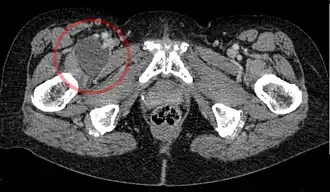

| _-_CT_axial_001_-_Annotation.jpg) Enlarged iliopectineal bursa in CT - scan | |

The iliopectineal bursa or the iliopsoas bursa is a large synovial bursa that separates the external surface of the hip joint capsule from the tendon of the iliopsoas muscle.[1]

The most proximal of part the iliopectineal bursa lies on the iliopubic eminence of the superior pubic ramus. The iliopectineal bursa passes across the front of the capsule of the hip joint and extends distally downwards almost as far as the lesser trochanter.[2]

The iliopectineal bursa frequently communicates by a circular aperture with the cavity of the hip joint.[1]

Inflammation of the iliopectineal bursa is called iliopectineal bursitis or iliopsoas bursitis.